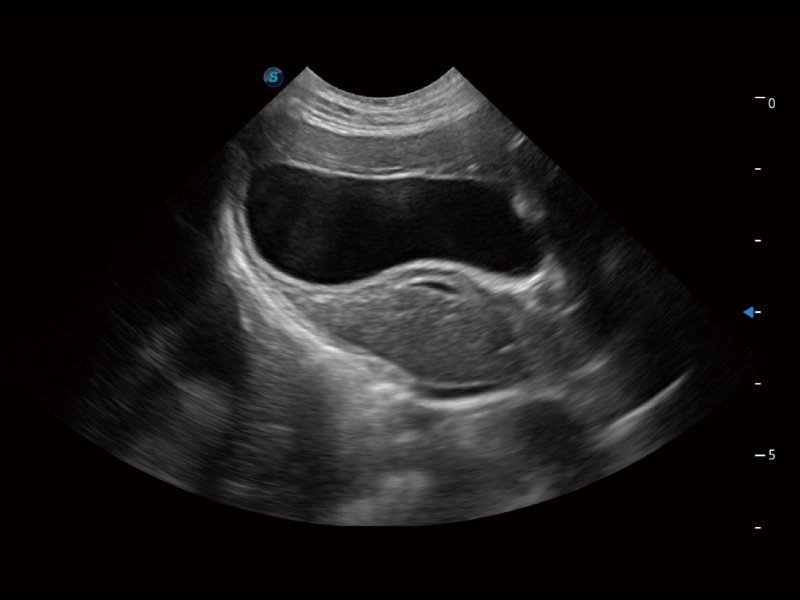

ProPet 70 进一步提升了微米成像算法,更加注重对基础原始图像的还原和保留,在有效减少斑点噪声、增强组织边界显示的同时,避免过度优化丟失真实的解剖信息。

一键自动识别膀胱壁及自动测量膀胱容积,不受膀胱形状和大小的限制,帮助医生快速精准获得测量的数据。

ProPet 70专为动物医生设计,对不同的动物体型和生理结构作出了针对性的优化。通过动物影像专用软件,可满足个性化的应用需求,帮助动物医生获得更精确的诊断数据。

为精细结构及组织边缘提供高清晰度的图像和更大的成像视野。帮助减轻医生的用眼疲劳,快速精准获得测量的数据。